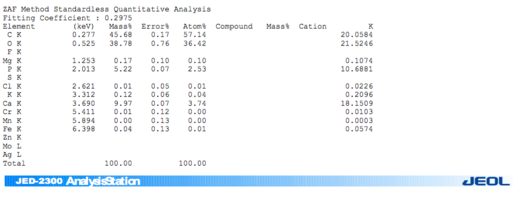

Химический состав минерализованного губчатого порошка.pdf

3. Полный точный химический состав материалов